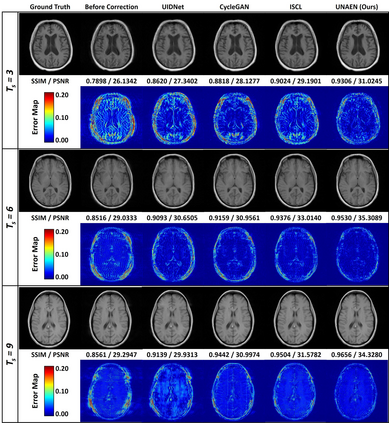

Motion artifact reduction is one of the most concerned problems in magnetic resonance imaging. In recent years, deep learning-based methods have been widely investigated for artifact reduction tasks in MRI. As a retrospective processing method, neural network does not cost additional acquisition time or require new acquisition equipment, and seems to work better than traditional artifact reduction methods. In the previous study, training such models require the paired motion-corrupted and motion-free MR images. However, it is extremely tough or even impossible to obtain these images in reality because patients have difficulty in maintaining the same state during two image acquisition, which makes the training in a supervised manner impractical. In this paper, we proposed a new unsupervised abnormality extraction network (UNAEN) to alleviate this problem. Our network realizes the transition from artifact domain to motion-free domain by processing the abnormal information introduced by artifact in unpaired MR images. Different from directly generating artifact reduction results from motion-corrupted MR images, we adopted the strategy of abnormality extraction to indirectly correct the impact of artifact in MR images by learning the deep features. Experimental results show that our method is superior to state-of-the-art networks and can potentially be applied in real clinical settings.